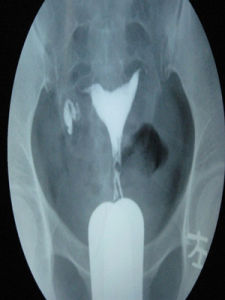

經X線片子閱讀

合格的造影是診斷的第一步,而明確的診斷卻是治療的關鍵,同一張片子不同的醫生由於經驗的不同會得出不同的結論,下面我們來看一些常見的片子。

1、正常的子宮輸卵管造影片子